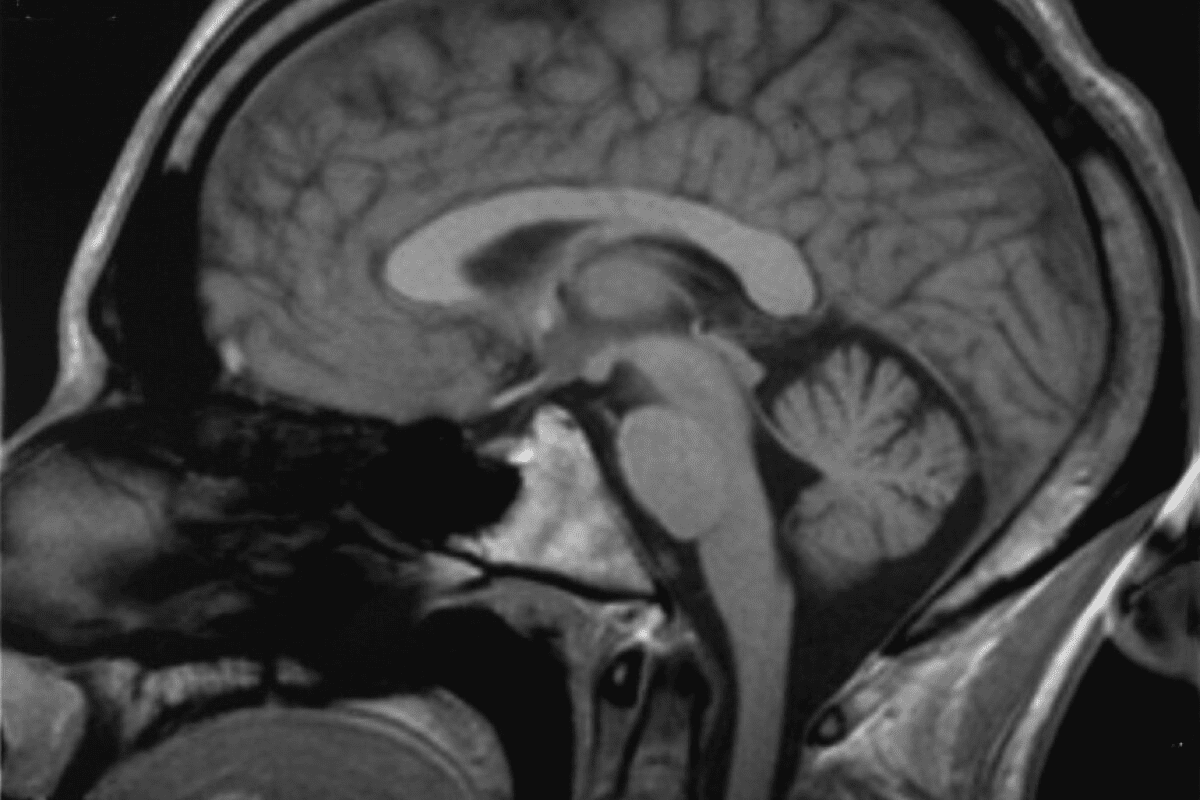

Imaging Techniques for Detection

- Magnetic Resonance Imaging (MRI): MRI is very sensitive. It gives clear brain images, showing where and how big the metastases are.

- Computed Tomography (CT) Scan: CT scans are fast and useful in emergencies. But they’re not as good as MRI for finding small metastases.

- Positron Emission Tomography (PET) Scan: PET scans help tell tumors apart from other brain issues.